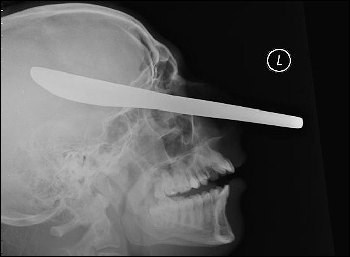

据英国《太阳报》2009年6月17日报道,28岁的英国小伙迈克尔·切希拉被人刺穿头骨竟然大难不死。一把用来抹黄油的刀从他的左侧脸颊穿过,直达他右侧的头盖骨,距离他的大脑只有1英寸(约2.5厘米)。日前迈克尔已经康复出院,而伤害他的凶手马克·默恩斯已被判入狱服刑。

餐刀插入头顶